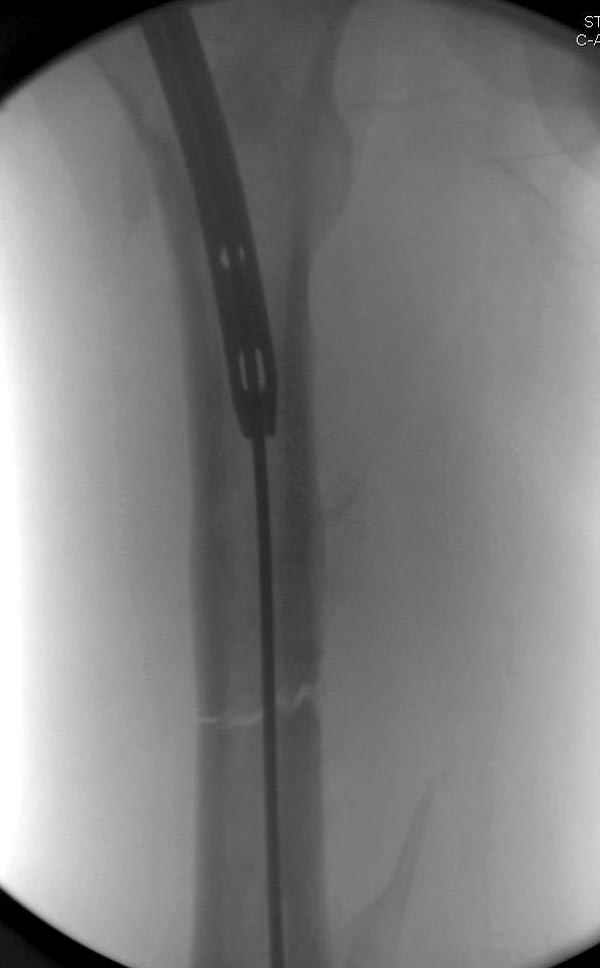

Рутинный интрамедуллярный остеосинтез с расверливанием и с фиксацией реконструктивным трокантерик штифтом (рис №1, №2),

если первые 4 месяца послеоперационного периода проходил без проблем, но на 5 месяце появились боли в дистальном отделе бедра и температура, т.е. симптомы медуллярного инфицирования (рис №3, №4).

Замена реконструктивного штифта “Custom made Nail” с антибиотиком (рис №5, №6),

после промывки канала с рассверливанием внутреннего кортекса, через 4 недели антибиотический штифт удалили, оспалителный процесс остановлен и бедро сросся.